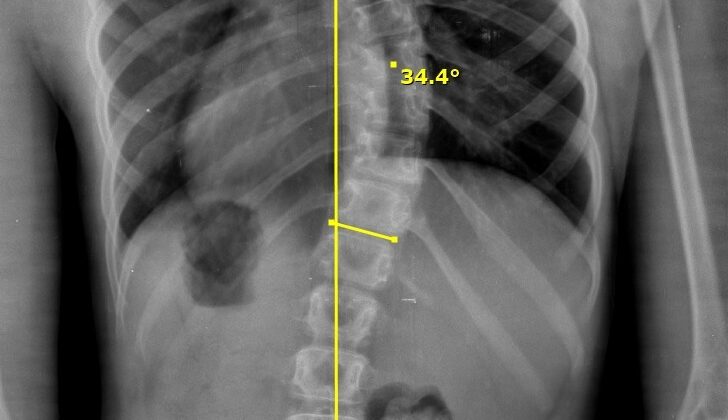

ثانيًا: أهمية قياس زاوية كوب (Cobb Angle)

تُعتبر زاوية كوب هي الطريقة العالمية الأساسية لقياس درجة اعوجاج العمود الفقري.

📌 كلما زادت الزاوية، زادت شدة الحالة.

قياس زاوية كوب

👉 بشكل مبسط:

- 10 إلى 24 درجة: اعوجاج بسيط

- 25 إلى 49 درجة: اعوجاج متوسط

- 50 درجة فأكثر: اعوجاج شديد

ومن المهم أن نفهم أن هذه الزاوية ليست رقمًا فقط، بل تساعد الطبيب على تحديد خطة العلاج المناسبة بدقة. لذلك، فإنها عنصر أساسي في متابعة الحالة.

ثامنًا: أهمية مناطق العمود الفقري

يُقسم العمود الفقري إلى مناطق مختلفة، وكل منطقة لها وظيفة:

📌 Thoracic (الصدري): مرتبط بالأضلاع

📌 Lumbar (القطني): أسفل الظهر

👉 وبالتالي، فإن تحديد مكان الانحناء يساعد في اختيار نوع العلاج المناسب سواء كان حزامًا أو تمارين أو متابعة.